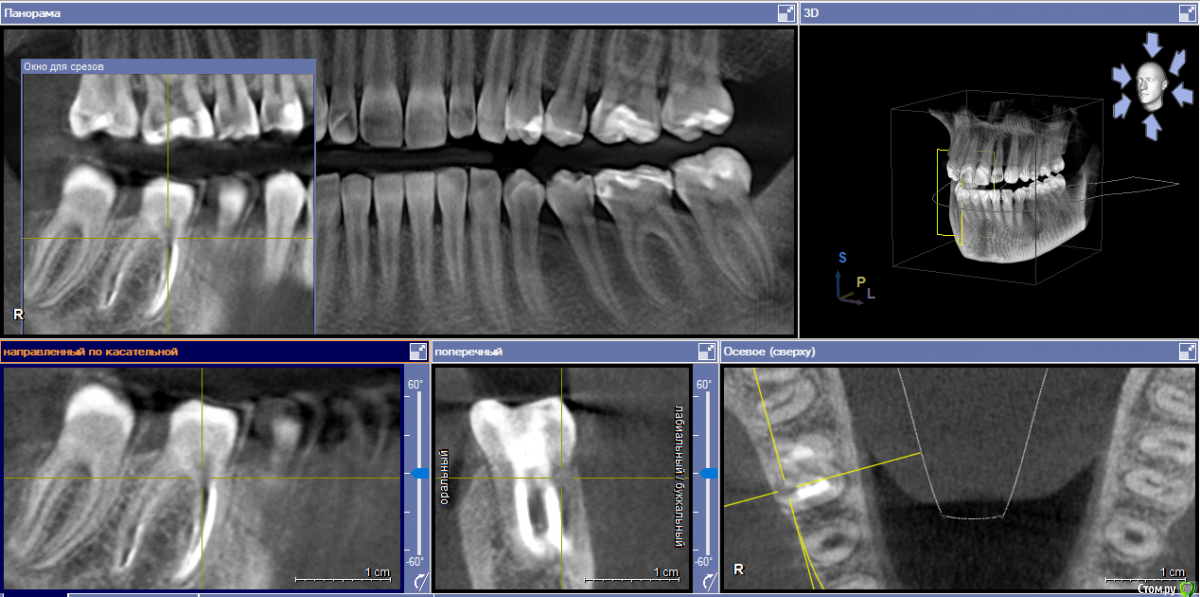

yellowborodova Опубликовано 5 января, 2020 Автор Поделиться Опубликовано 5 января, 2020 Здравствуйте... всех с праздником)) прошу прощения, что так долго... вот срезы кт и панорама. Надеюсь, заскринила то, что нужно)) буду рада, если у кого-либо будет желание и возможность прокомментировать тему. Ссылка на комментарий

yellowborodova Опубликовано 5 января, 2020 Автор Поделиться Опубликовано 5 января, 2020 Ссылка на комментарий